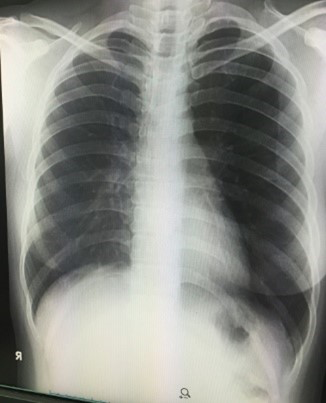

胸部X線レントゲンは肺がん検診の一般的な検査ですが、右のような1枚の写真を撮影し、診断を行います。

胸部レントゲンは1方向(正面)、もしくは2方向(側面)からの画像のため、病変が心臓や大血管、骨などと被ると確認できなくなります。

また、早期癌でよくある淡い病変はそもそもレントゲンでは写らないのです。

その点CTは心臓や大血管、骨の影響を排除できますし、淡い病変もはっきりと確認できるため早期発見につながるのです。